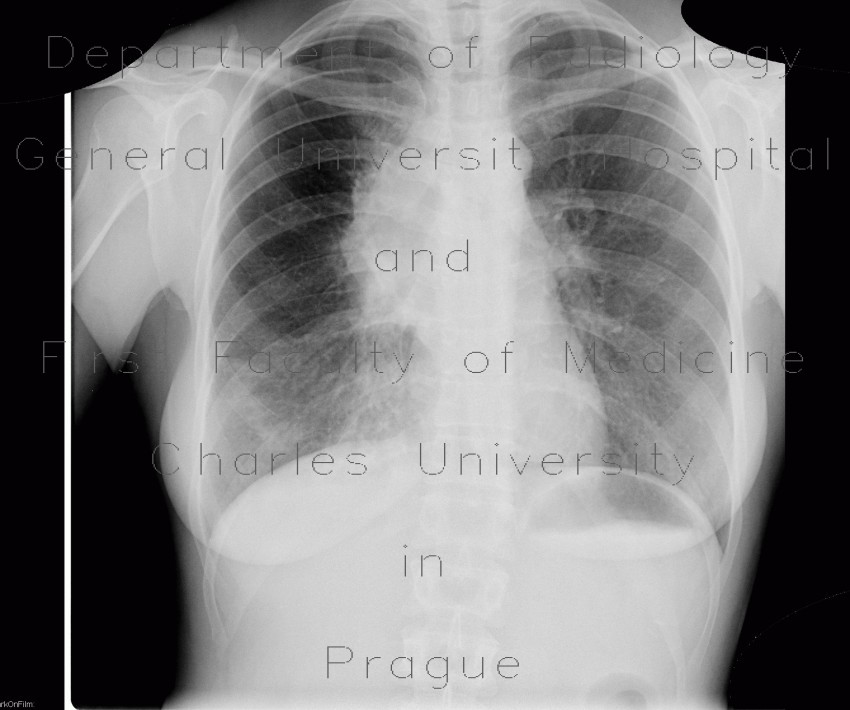

Volume 50 Number 12 December 2002 Primary pulmonary lymphoma 535 abscess. Because pulmonary lymphoma is not distin-guishable radiographically from primary lung cancer ... Read Document